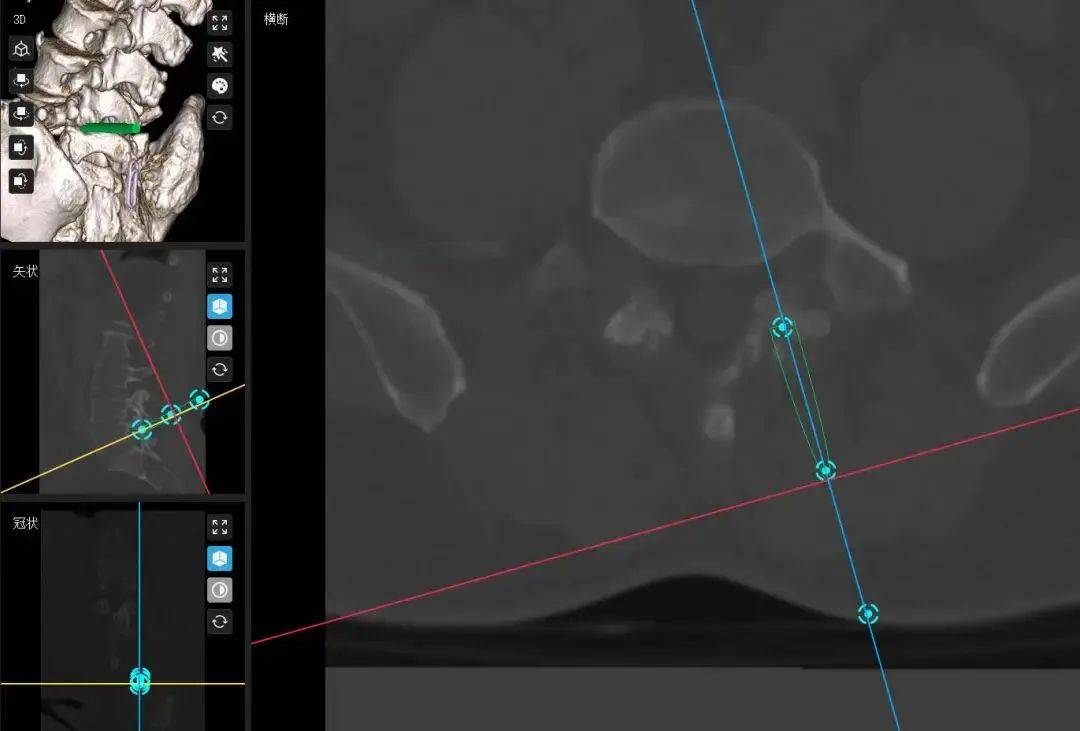

61岁男性,因腰腿痛及双下肢麻木入院,查体示双侧小腿外侧及足底感觉减退(左重)、左直腿抬高试验阳性、肌力下降。影像确诊L4/5右侧椎间盘突出伴左侧髓核脱垂至椎弓根内缘,合并L5稳定峡部裂。

采用数字化虚拟精准重建、规划,导航实现毫米级定位,避免神经损伤,硬膜波动恢复良好。术后验证数字技术可缩短学习曲线,提升复杂病例操作安全性与病灶清除率,为脊柱微创标准化提供新范式。